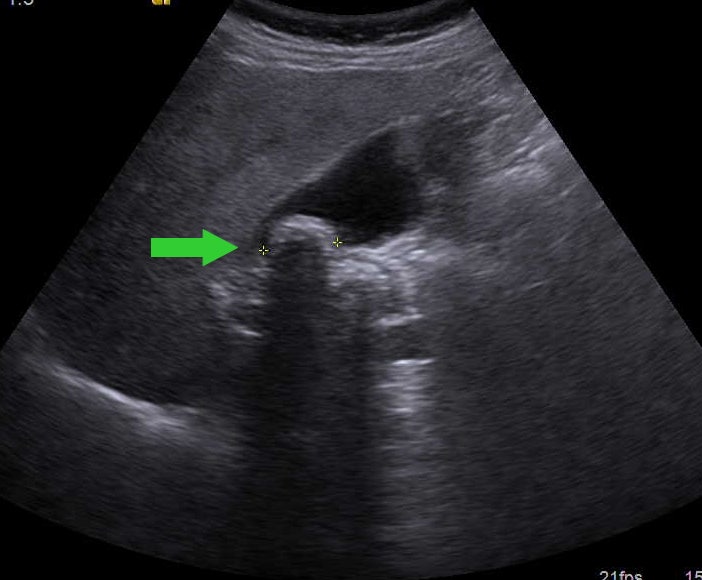

담석증 검사-복부 초음파 검사-담석은 CT나 X선으로도 확인하기 어려운 경우가 많으며, 일차적인 검사는 복부 초음파 검사입니다.

담석의 복부 초음파 영상 초음파 소견에서 놓치지 말아야 할 것은 음향 그림자(acoustic shadow)입니다.